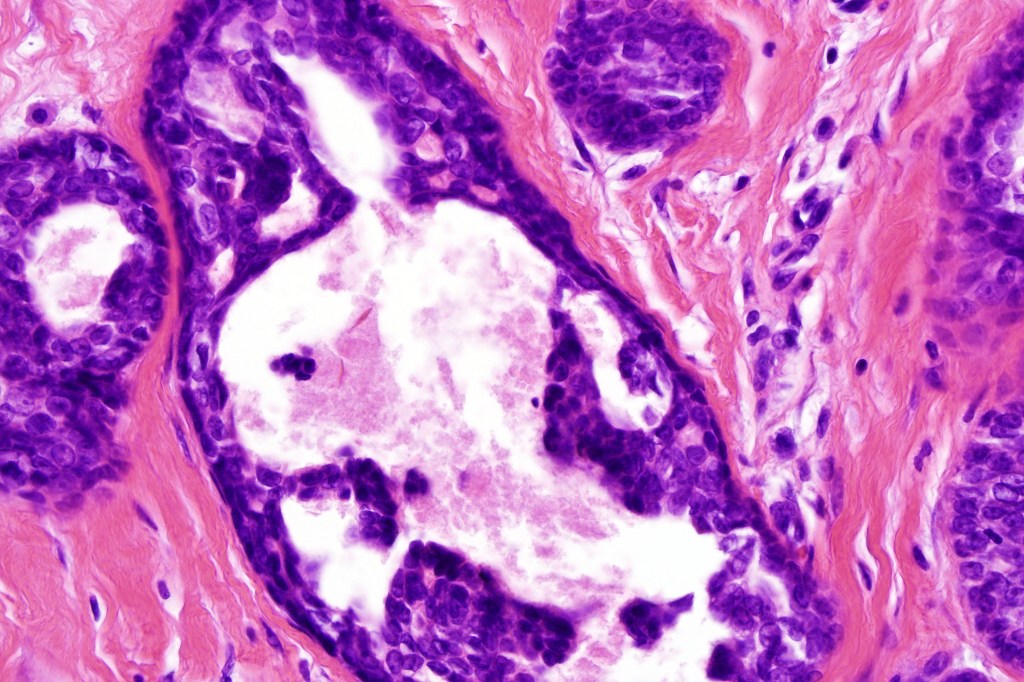

•Ducts lined by double-layered epithelium- small inner, uniform cells with eosinophilic cytoplasm & vesicular/hyperchromatic nuclei with small nucleoli & outer myoepithelial cells

•No pleomorphism and mitoses are sparse of absent

•Pseudo-papillae (devoid of a fibrovascular core) are often conspicuous

Absense of true papillae (i.e with a fibrovascular core)

•Variable cribriform pattern